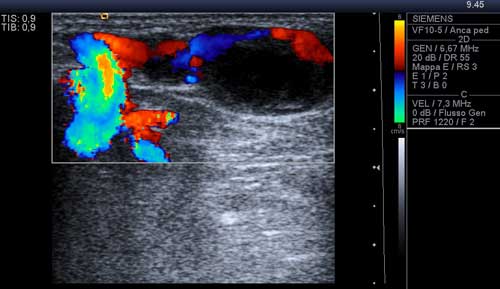

immediatamente a valle della biforcazione della arteria pedidia nel

ramo plantare profondo e nella 1a metatarsale dorsale,

arteria che appariva decorrere, sia pure in maniera irregolare, lungo

la parete mediale della formazione (Figura 2)

Figura 2. Componente vascolare della neoformazione a valle della biforcazione della arteria pedidia. Nello spessore dello strato pi� esterno si dimostrava la presenza di un flusso ematico bidirezionale (Figura 3) ![]() | |

Figura 3. Presenza di flusso in parete. � stata effettuata una RMN con contrasto con acquisizioni multiplanari T1 e T2 pesate anche con tecnica di soppressione del grasso, con il rilievo di una formazione ovalare di 16 x 12 x 20 mm a margini regolari con iperintensit� di segnale centrale nelle pesate T1 e T2 dipendenti, e componente periferica sottile che subisce enhancement contrastografico, in apparente continuit� anatomica con struttura vascolare del fascio vascolo-nervoso dorsale, ascrivibile, in primis, a formazione vascolare o patologia vascolare dilatativa trombizzata (Figure 4, 5 e 6). ![]() |